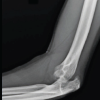

A 77-year-old male with right knee pain was diagnosed with advanced OA. In pursuit of relief, the patient underwent GAE at another hospital. Following the procedure, the patient developed swelling, increased pain, and skin discoloration, necessitating readmission to the same hospital for vascular observation and pain control. Redness, swelling, and pain subsided over a period of 7 days, and the patient was discharged from the hospital (Fig. 1). After a 6-month recovery period, owing to persistent osteoarthritic knee pain, the patient sought further treatment options at our hospital. Upon consultation with our radiologists, an arteriogram was performed 1 year after embolization, and it was ascertained that the genicular arteries remained patent (Fig. 2). Consequently, a decision was made to proceed with total knee arthroplasty to manage OA. During arthroplasty, bone samples of bone cuts from the weight-bearing distal femur and proximal tibia were sent for histopathological examination, and the results were negative for osteonecrosis (Fig. 3). The post-operative period involved meticulous monitoring of complications such as wound dehiscence, tissue necrosis, and infection. Fortunately, aside from the mild erythema observed around the knee a week after the procedure, which did not require any treatment, the wound healed well without any complications, with standard rehabilitation of same-day walking, and ROM exercise could be initiated (Fig. 4 and 5). After 1 year of follow-up, the patient experienced relief of knee pain and achieved a knee range of motion of up to 0°–120° and back to his day-to-day activities, indicating a successful outcome following total knee arthroplasty (Fig. 6 and 7).